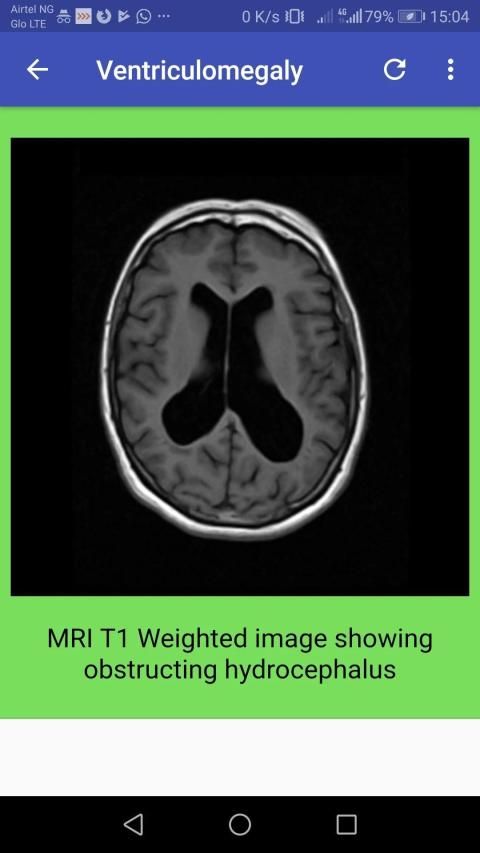

Computed tomography, more commonly known as a CT or CAT scan, is a diagnostic medical test that, like traditional x-rays, produces multiple images or pictures of the inside of the body.

The cross-sectional images generated during a CT scan can be reformatted in multiple planes, and can even generate three-dimensional images. These images can be viewed on a computer monitor, printed on film or by a 3D printer, or transferred to a CD or DVD.

CT images of internal organs, bones, soft tissue and blood vessels provide greater detail than traditional x-rays, particularly of soft tissues and blood vessels.

Computed tomography (CT) scanning of the head uses a series of x-rays of the head taken from many different directions; the resulting data is transformed into a series of cross sections of the brain using a computer program.